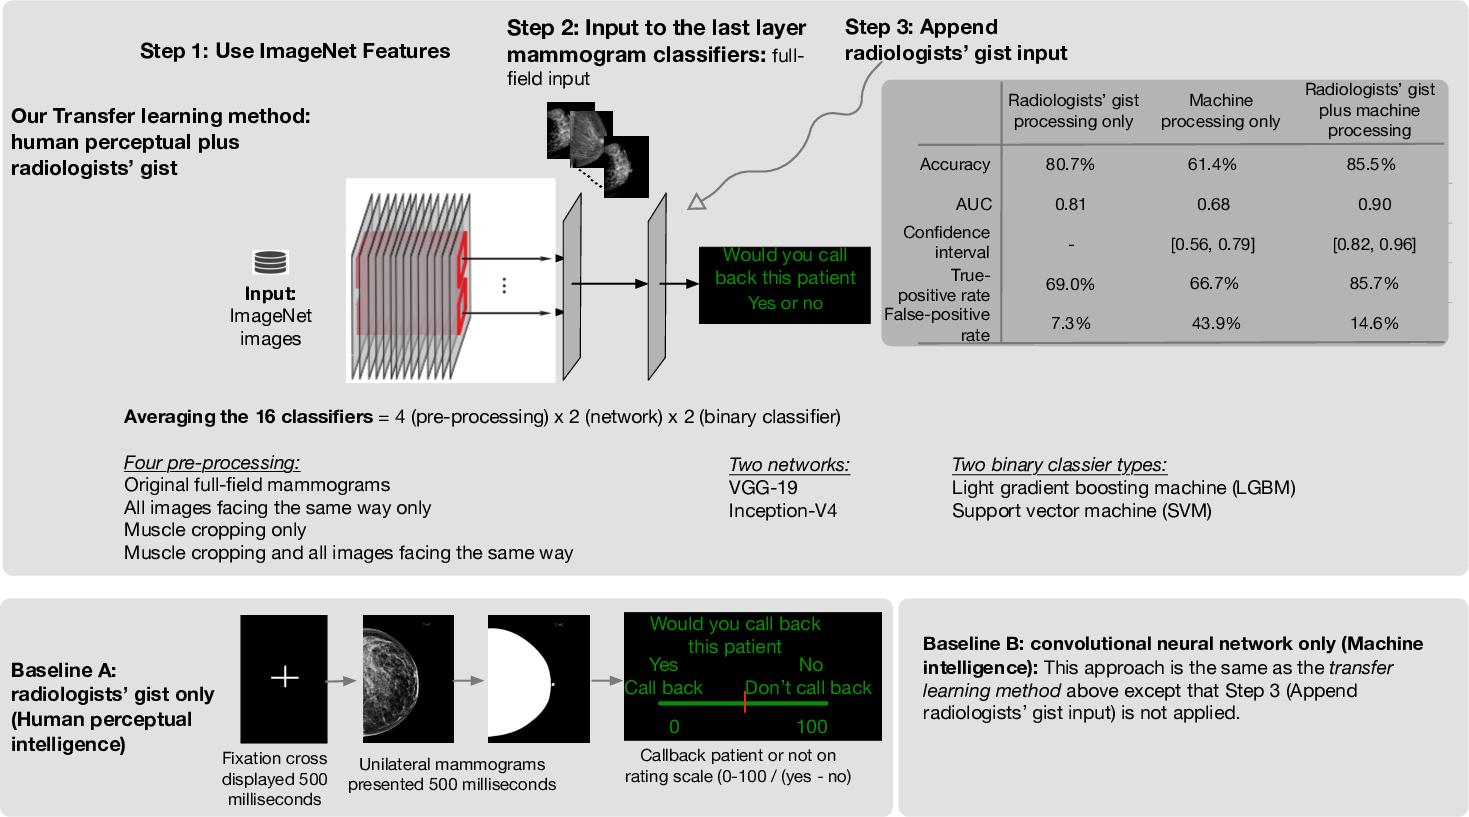

Radiologists can classify a mammogram as normal or abnormal at better than chance levels after less than a second’s exposure to the images. In this work, we combine these radiologists’ gist inputs into pre-trained machine learning models to validate that integrating gist with a CNN model can achieve an AUC (area under the curve) statistically significantly higher than either the gist perception of radiologists or the model without gist input.

In this work, we hypothesize that a CNN (aka, machine intelligence) plus the information from radiologist experts (aka, human perceptual intelligence) will provide more accurate results than either the radiologists or the CNN alone. Our goal is not to generate a novel CNN architecture for screening, but instead add radiologist response in input to models already used.

We use a transfer learning approach to combine radiologist gist information with features from a CNN classifier to investigate the benefits of coupling the machine and human expertise (Figure 1). Our method begins with the preprocessing of input dataset of mammogram images with four methods: (1) no changes, (2) horizontally flip all left breast images, (3) crop muscle fibers out of each image, (4) combine (2) and (3), i.e., crop muscle fibers out and then horizontally flip all left breast images. When we horizontally flip left breast images, our resulting dataset will have images that face the same direction. Next, we feed each dataset into established CNNs Inception-v4 and VGG-19, pretrained on ImageNet, a corpus of over 14 million non-medical images [8]. Though these networks are meant to classify non-medical objects. we use deep features to provide an abstract representation from within the network to classify mammograms. Usually these features are unintelligible to humans, but some describe intuitive aspects of an image, such as edges, spirals, or gradients. In each network, we take all values from neurons of one layer near the final classification layer to obtain our feature vector. Finally, we perform classification based on the feature vector obtained from the CNN using LightGBM (LGBM) [9] and a linear support vector machine (SVM). Putting together, we have 4 processing steps of muscle cropping and rotation, two CNNs for deep features, and two classifiers for final classification, giving us end-to-end systems.

We test these 16 systems with and without appending the radiologist gist responses to the end of the feature vector before classification. Original radiologists scores for detecting breast cancer were in range [0,100]. Radiologists’ input is set to 0 (normal) if the average response is greater than 50 and to 1 (malignant) otherwise. We also calculate a “confidence score” from the radiologist gist input for each image: .

Our baseline condition (A) is the radiologists-alone condition in Evans et al. [5] (Figure 1 lower-left): radiologist gist data are gathered by showing radiologists a unilateral mammogram of a mammogram image with no abnormalities, an image with an abnormality, or an image contralateral to an image with an abnormality for 500 milliseconds each. They perform at an above-chance level at classifying abnormal and normal mammograms in our dataset, with an accuracy of and an area under the receiver operating characteristic curve (ROC and AUC) of 0.81 (Figure 2).

Our baseline condition (B) is the CNN-alone condition, when classifiers do not use radiologist gist response in the input vector (Figure 1 lower-right and AUCs in Figure 2, darker blue bars). Our end-to-end models on average achieve an AUC of 0.656. Also, only one of the resulting AUCs (AUC = 0.828) from these 16 CNN-alone classifiers is better than the radiologist baseline of 0.809. The confidence interval (CI) is ) with the following system: preprocessing option 2 on inputs (input images facing the same direction), fed through VGG-19 for the features, and finally classified with a linear SVM. We think overall this CNN-is-largely-worse-than-human may be due to our dataset being relatively small compared to other mammogram screening datasets.

Our new systems are to combine the baseline condition (B) with the radiologists’ input (Figure 1 top and AUCs in Figure 2 lighter blue bars). We see substantial improvements to the baseline B models when we add radiologist gist response into the classifier’s input in CNNs, with these new classifiers outperforming radiologists in some cases. The average AUC of the 16 classifiers increases to 0.814. On average, each classifier improves its AUC by 0.157, reduces the false positive rate (FPR) by 0.188, improves the true positive rate (TPR) by 0.101, and improves accuracy by 0.144. In all cases, AUC, accuracy, true-positive rate (TPR), and false-positive rate (FPR) improve when adding radiologist gist response to the input vector, except for one that had a small decrease in TPR. In 10 of the 16 classifiers that use radiologist gist response in the input vector, we observe an AUC higher than the radiologists’. One result reports an AUC of 0.899, achieved with preprocessing option 2 (flip all left breast images) before feeding the inputs to Inception-v4 for the feature vector and then using LGBM for classification. Further, this stand-out case from our tests approaches the AUC of specifically trained deep network for the same task [10].